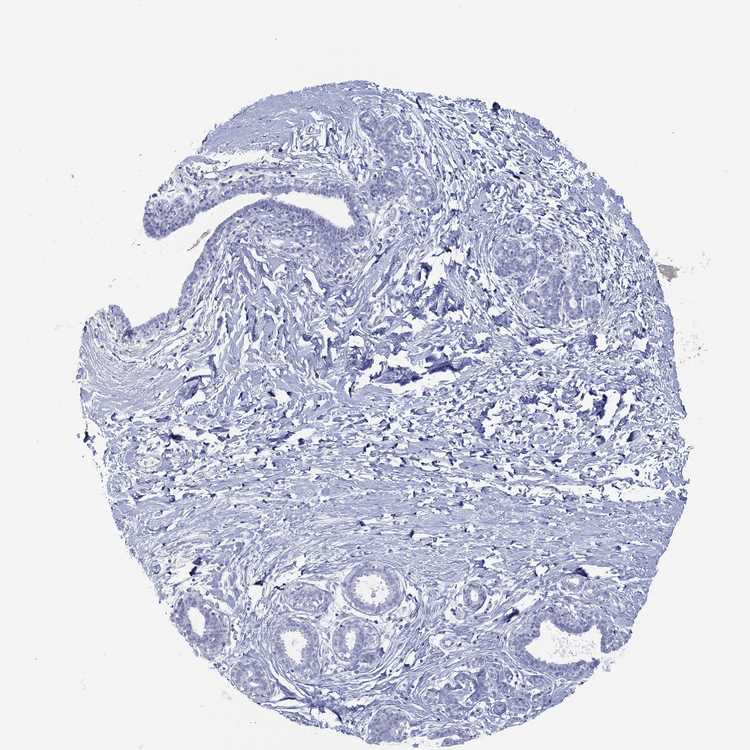

BREAST - Antibody stainingi

Antibody staining in the annotated cell types in the current human tissue is reported as not detected, low, medium, or high, based on conventional immunohistochemistry profiling in selected tissues. This score is based on the combination of the staining intensity and fraction of stained cells.

Each image is clickable and will lead to virtual microscopy that enables deeper exploration of all samples and also displays staining intensity scores, fraction scores and subcellular localization as well as patient and tissue information for each sample.

Antibody HPA078713

Adipocytes Not detected

Glandular cells Not detected

Myoepithelial cells Not detected